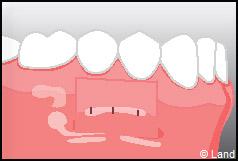

LES TECHNIQUES AVEC APPORT DE GENCIVE OU « GREFFE DE GENCIVE » :

Elles font appel à un prélèvement sur le patient à un endroit où elle est en excès, qui est ensuite posé sur la récession.

Les greffes épithélio-conjonctives :

Elles sont pratiquées pour des zones non esthétiques de la cavité buccale, à cause de l’aspect « rustine» que la cicatrisation leur confère.